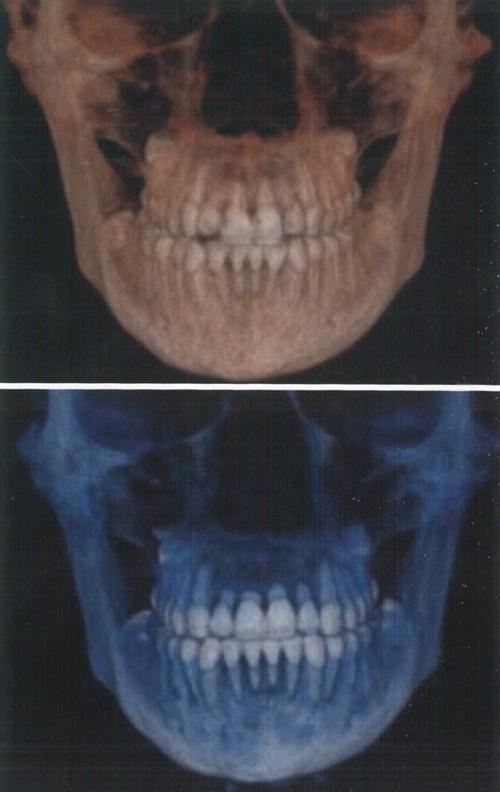

- 根尖片:常规检查手段,可显示牙根长度、形态变化,但对颊舌向吸收敏感度低;

- 曲面断层片:用于评估全口牙根吸收情况,但存在影像重叠,易漏诊轻微吸收;

- CBCT:目前诊断金标准,可三维、多层面显示牙根吸收的部位、范围和程度,精准量化吸收量(如吸收深度占根长比例)。